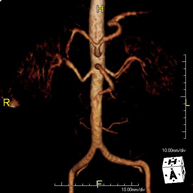

- Abdominal aorta MRI angiography

A non-invasive diagnostic test that involves studying the abdominal aorta, obtaining high-definition anatomical images using an electromagnetic field and radio waves (with transmitter and receiver). The use of paramagnetic intravenous contrast (gadolinium) is essential. However, it is a radiation-free procedure. The quality of the images allows for 2D and 3D reconstructions. It is indicated in patients with vascular disease (atherosclerosis), aneurysm studies, pre-surgical studies of lesions adjacent to the abdominal aorta as a vascular ‘map’, etc.

- Iliac aorta MRI angiography

A non-invasive diagnostic test that involves studying the abdominal aorta, obtaining high-definition anatomical images using an electromagnetic field and radio waves (with transmitter and receiver). The use of paramagnetic intravenous contrast (gadolinium) is essential. However, it is a radiation-free procedure. The quality of the images allows for 2D and 3D reconstructions. This test is particularly recommended as a pre-surgical study (vascular map) prior to percutaneous or surgical interventions on the abdominal aorta, as a complementary study in patients with lower limb ischaemia, etc.